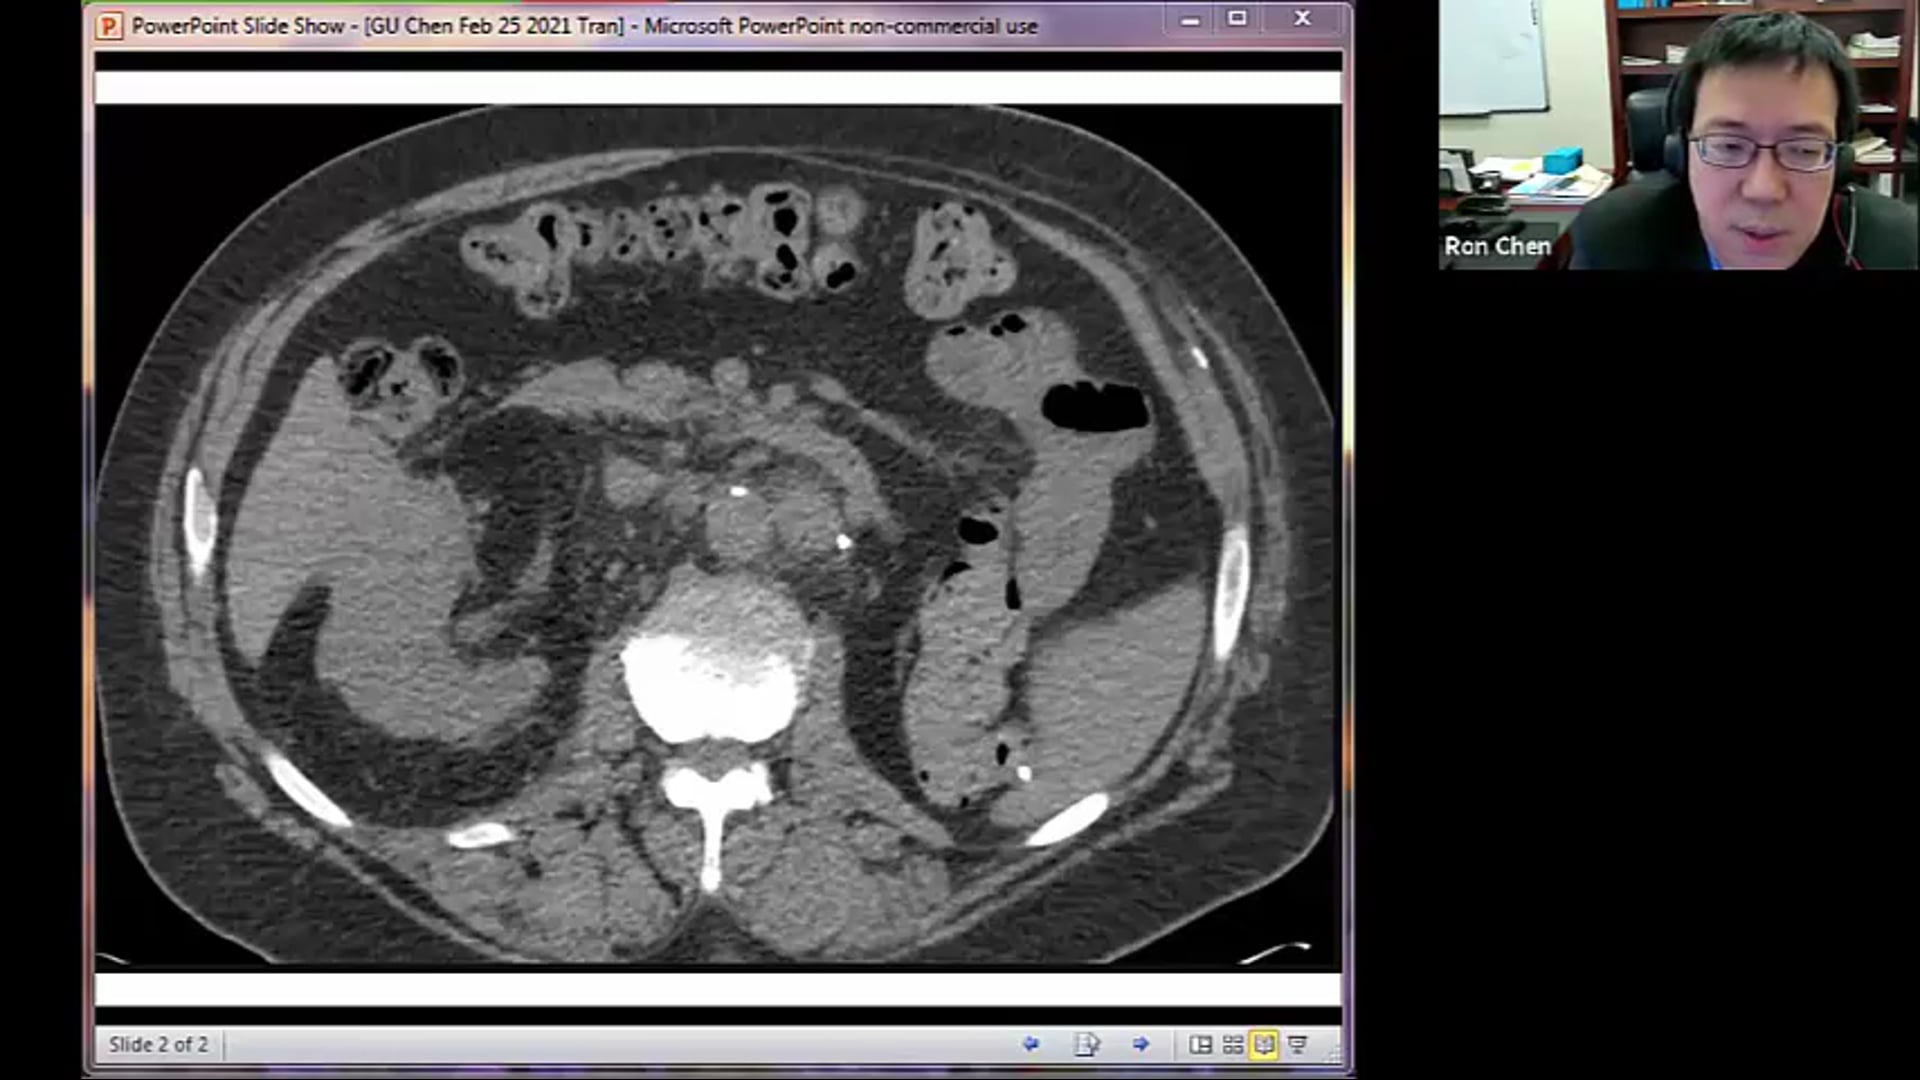

02/25/21 - Dr. Ronald Chen - Radiation Oncology - GU US

Renal cell CA, recurrent renal cancer, kidney mass, SBRT, small bowel dose constraints, bladder management during treatment, boost dose,